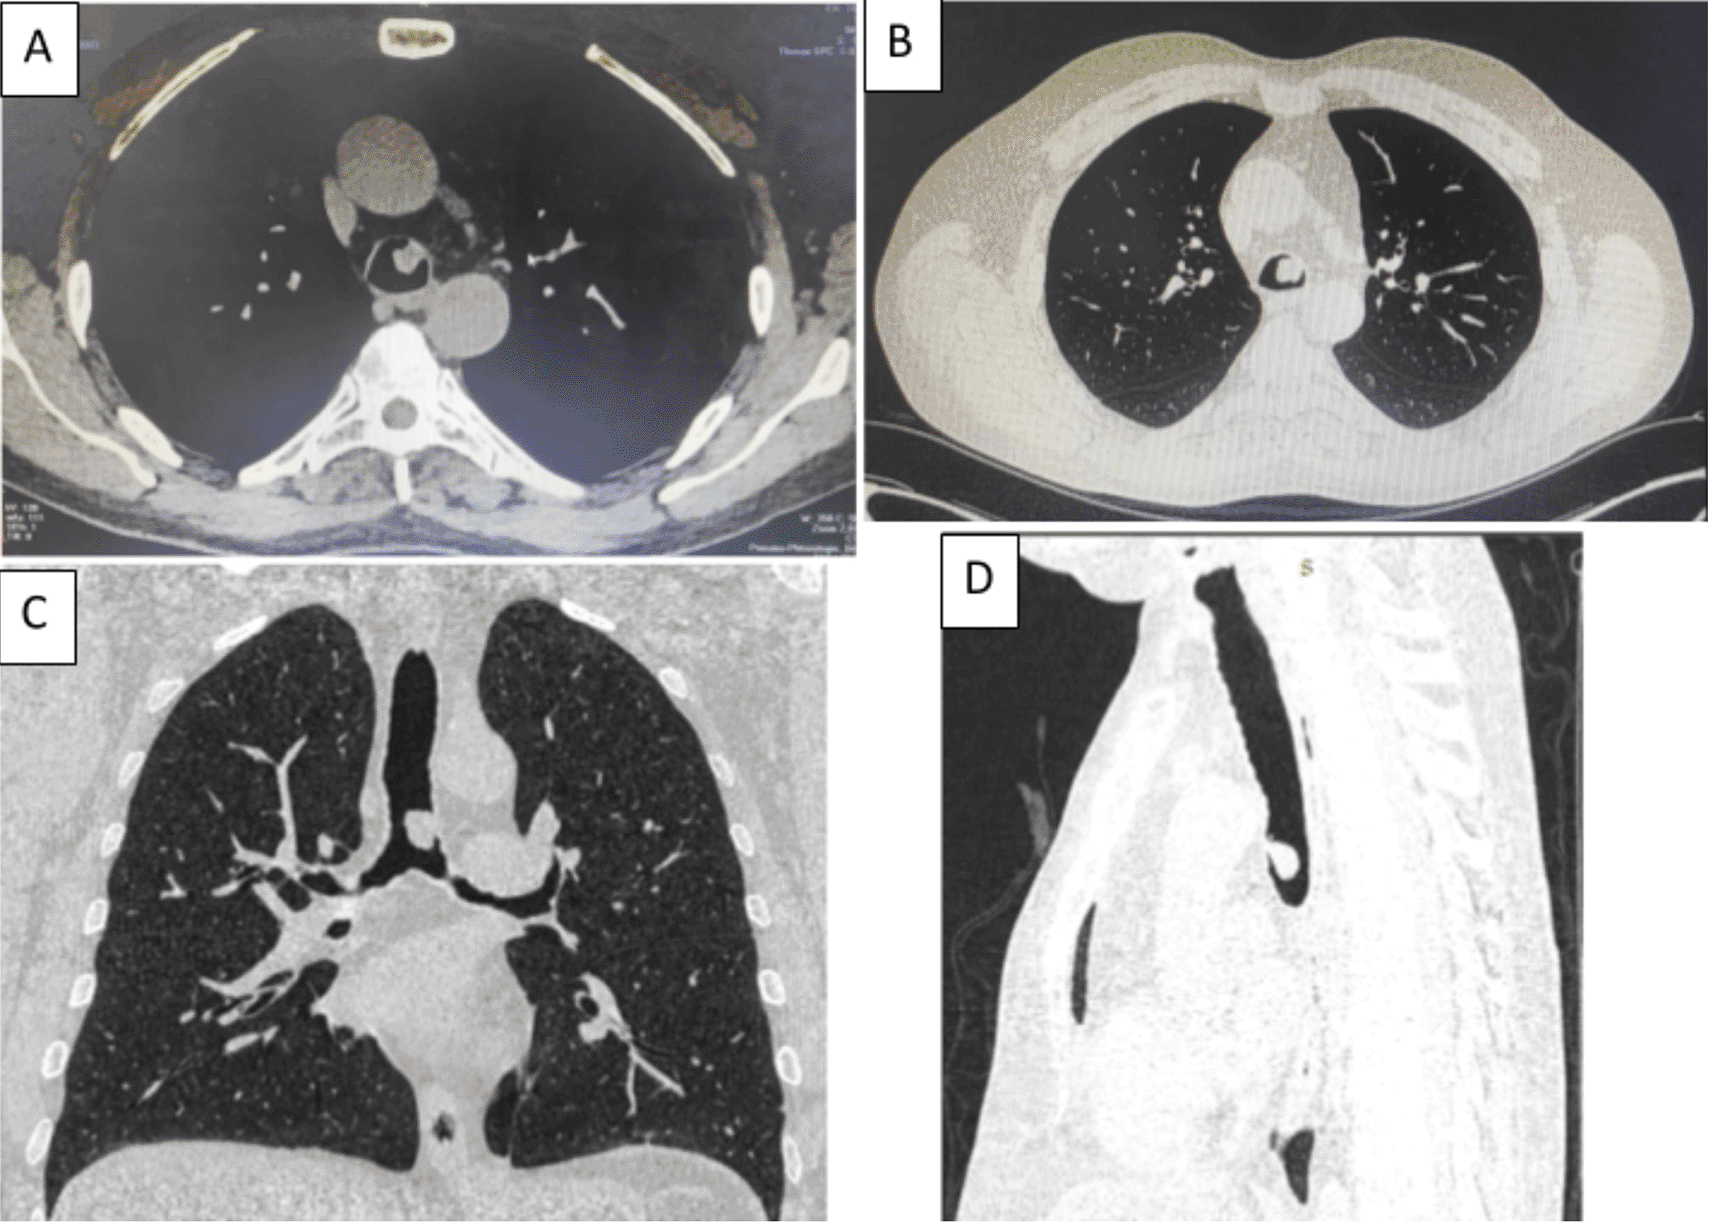

A 58-year-old male with a continued 70-pack-year smoking history was referred to our department for the endoscopic treatment of an endotracheal tumor. Four years previously, the patient presented with isolated shortness of breath and was treated for chronic obstructive pulmonary disease (COPD). Physical examination showed wheezes, and spirometry had met the GOLD criteria for the diagnosis of COPD with very severe airflow limitation (post-bronchodilator FEV1: 1.02 L (29%), post-bronchodilator FEV1/FVC ratio: 45%). The patient was subsequently hospitalized for bilateral hypoxemic pneumonitis and acute respiratory failure, which was treated as COPD exacerbation with a good evolution under usual treatment. On admission in our department, his clinical examination was normal, and his oxygen saturation was 97% (room air). Laboratory tests and chest radiography revealed no abnormalities (Figure 1). Chest computed tomography (CT) scan showed a hypodense pedunculated budding lesion of the left anterolateral tracheal wall located just above the carina, 12 cm from the vocal cords and measuring 17 × 15 × 10 mm (Figure 2). Flexible bronchoscopy confirmed an endotracheal lesion, but biopsies were non-contributory. Based on these findings, laser-assisted mechanical resection of the tumor has been validated as a feasible treatment option. Rigid bronchoscopy, performed under general anesthesia, revealed a non-vascularized pale pink tumor located at the lower third of the trachea approximately 1 cm distal to the carina, which obstructed 60% of the tracheal lumen (Figure 3A). Following the initial exploration, the tumor was removed at the tip of the bronchoscope following laser treatment (15W,364 J). No other instrument was used. On the final examination, a small tumor residue was observed (Figure 3B). There were no complications, and the patient was rapidly discharged. The tumor measured 18 × 10 mm (Figure 4). Histopathological examination of the samples stained with Hematoxylin and Eosin (H&E) showed the presence of hypertrophic seromucous gland admixed with variable amounts of fibrous adipose tissue, spindle cells, and myxoid stroma (Figure 5). The diagnosis of endobronchial HC was established. The patient subsequently underwent follow-up flexible bronchoscopies, which all revealed that the tumor residue was stable and did not obstruct the tracheal lumen with a follow-up of three years (Figure 6). The patient is currently asymptomatic, and his last spirometry examination revealed no abnormalities.